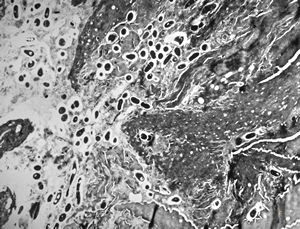

M,59y. | Histoplasma capsulatum - lung